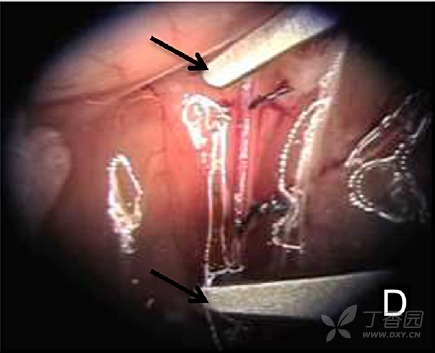

图 D. 用血管夹夹闭股动脉和股静脉

图 E. 用 27 G 穿刺针行股静脉、动脉切开